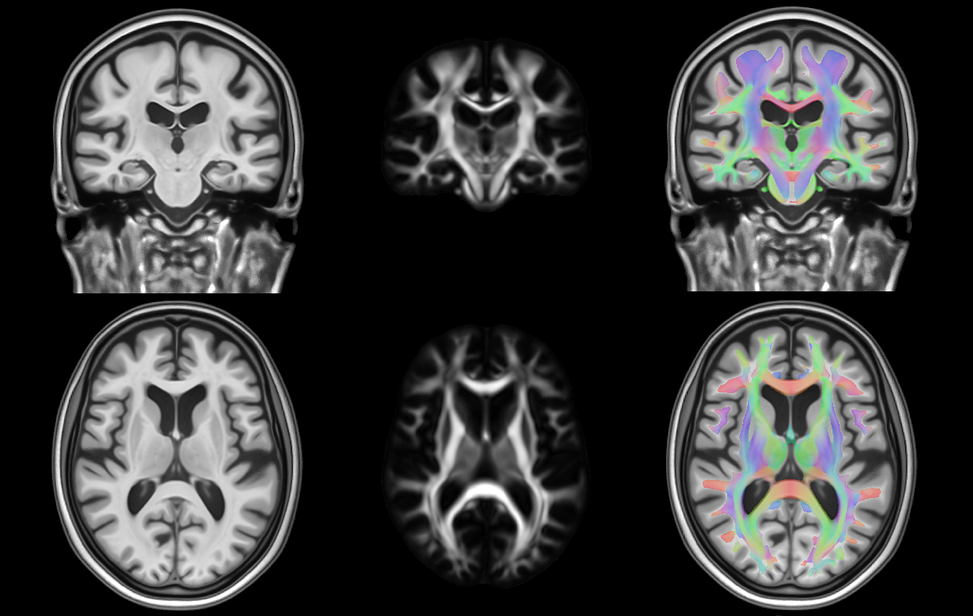

Slide background IIT Human Brain Atlas v.5.0 Anatomical Templates DTI Template HARDI Template Gray Matter Labels Multi-Layer White Matter Labels Download Now

The mission of the Magnetic Resonance Imaging Lab at the Illinois Institute of Technology (MRIIT for short; pronounced 'emrit ) is to develop in-vivo and ex-vivo MRI methods and neuroimaging resources, and to apply these technical developments towards the diagnosis and monitoring of brain disease.

MRIIT is home of the IIT Human Brain Atlas (young adult atlas), the MIITRA Atlas (older adult atlas), and the ARTS biomarker. All resources are publicly available.

Current research at MRIIT focuses on: a) human brain atlases, and b) multi-modal in-vivo and ex-vivo MRI in aging and dementia. Just a few examples of our projects are:

• Development of brain atlas resources for neuroimaging research